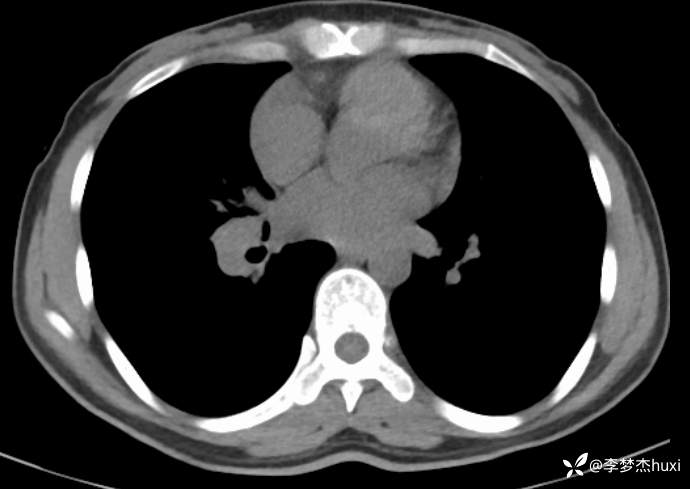

女性35岁,主因咳嗽、咳痰1月,胸部CT报肺炎,猜对乃神医!

女, 35 岁,主因咳嗽、咳痰1月于2025-11-05 08:46入院。

1.现病史:患者中年 女,患者于入院前1月“感冒”后出现咳嗽、咳痰,为黄白痰,不易咳出,无痰中带血,咽部刺痒不适,咳嗽明显,无胸痛,无胸闷、憋气,无恶心,未呕吐,无腹痛、腹泻,无尿频、尿急、尿痛,于院外口服药物(具体不详)治疗,病情未见好转,2025-11-4于我院门诊查胸部CT提示右肺炎症。为进一步诊治来我院;门诊以“肺炎”收入院 。

肺炎。